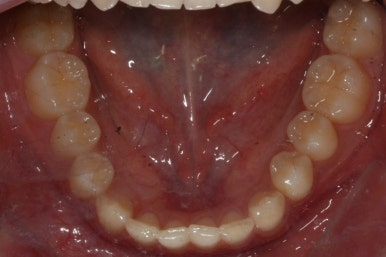

위 사진들은 부산매복치아교정 키다리아저씨치과에 처음 내원하셨을 때의 모습입니다.

화살표 표시한 부분이 바로 영구치 송곳니가 있어야 할 자리인데, 매복이 되어있고 대신 유치가 여전히 남아있는 모습입니다.

부산매복치아교정 상악 부분교정을 통해 매복치를 교정해준 이번 치료의 전후사진 비교입니다.

썩은 유치 대신 영구치 송곳니는 매우 자연스럽게 위치되었습니다. 아랫니는 교정하지 않았기 때문에 약간 삐뚠 느낌은 남아있지만 맞물림은 크게 문제가 없게 마무리 되었습니다.